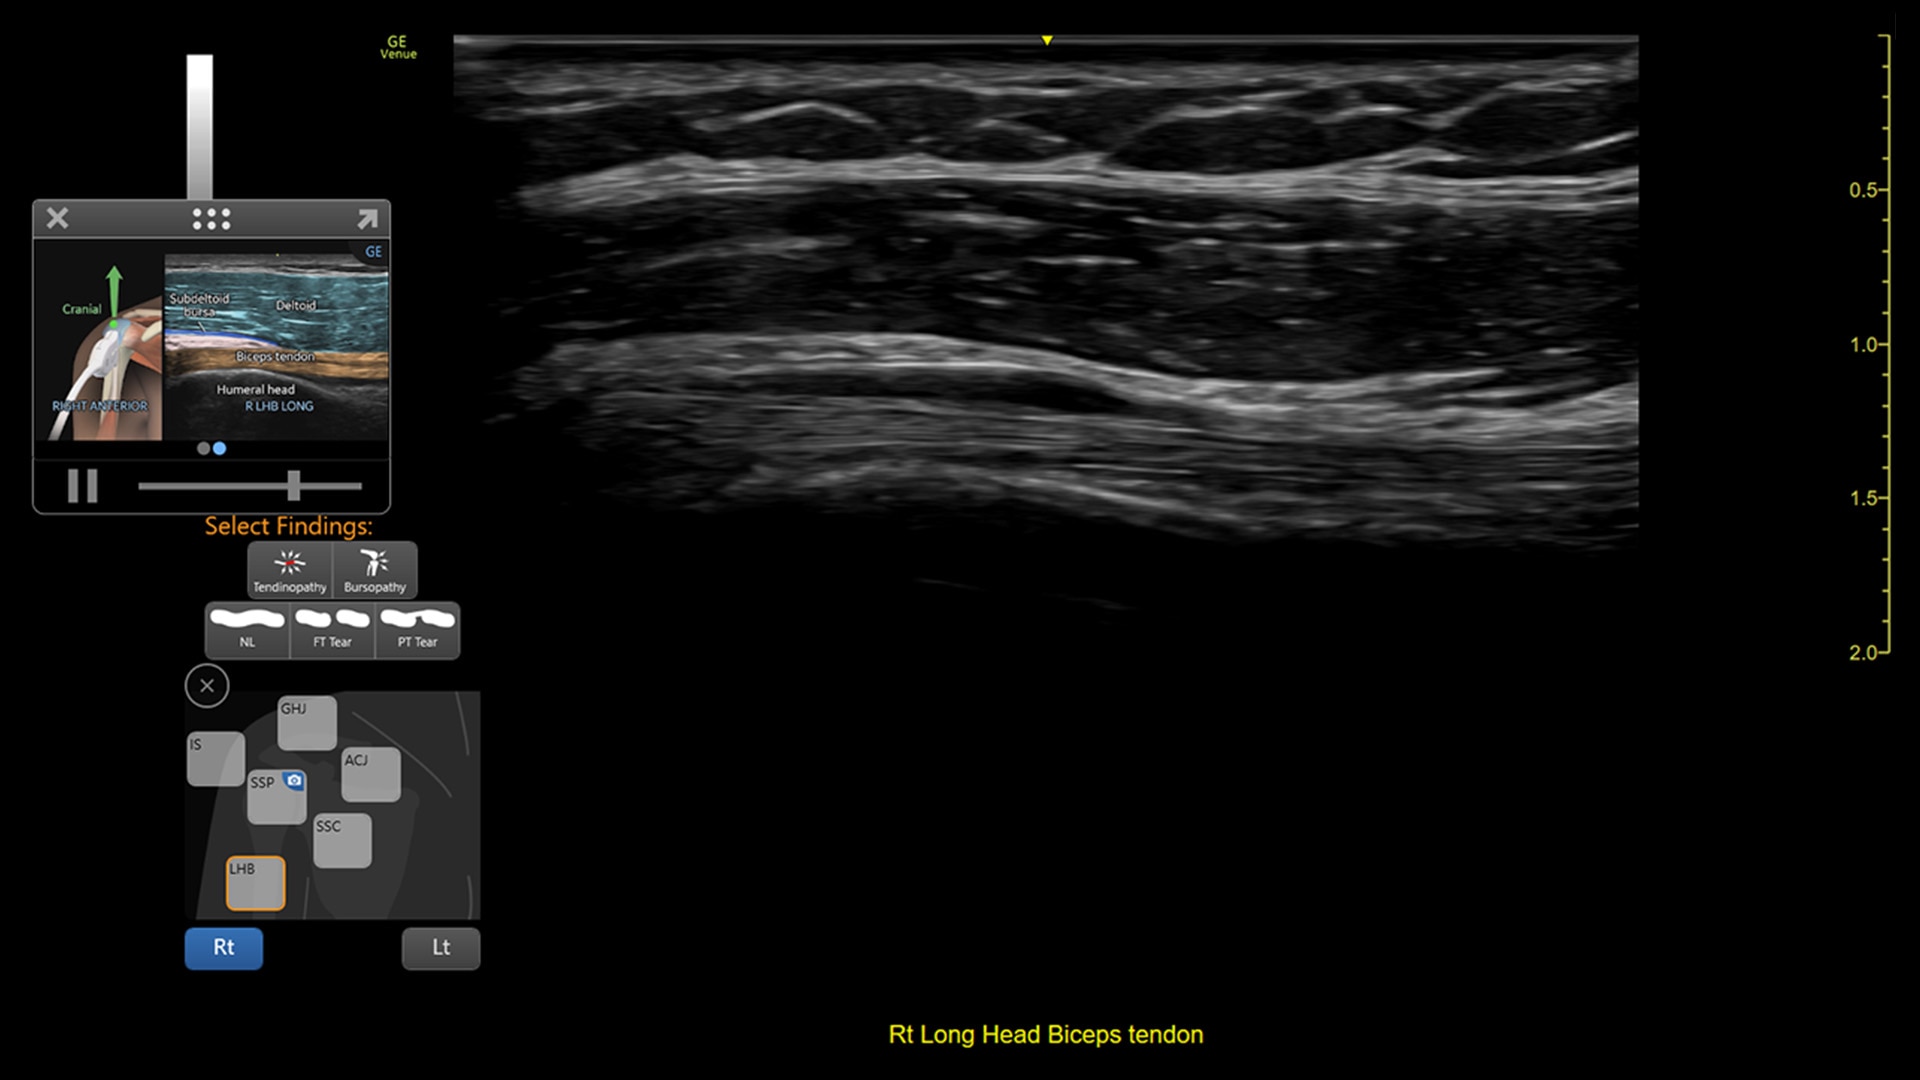

VENUE COACH MSK

Simplifying MSK scans

This easy-to-use exam documentation tool assists users through exams by providing reference images and anatomy markups. Multiple anatomical areas and helpful video tutorials help clinicians to acquire the scans they need.

Focus areas include:

• Shoulder

• Knee

• Hip

• Elbow

• Wrist/Hand

• Ankle/Foot

• MSK Diagrams: Simplifies documentation and assists the clinician in follow up for patients. No need to manually type findings—you can simply assign a label from a pre-populated list that correlates with the images. Get a single view diagram with one click image storing, keep track of assessments and show trends in response to therapy.

• Reference Image: Reference image provides anatomy mark-ups to assist novice users in scanning the correct anatomy

• Bilateral mode: Helps you to view the opposite side of the same zone for comparison (available for Shoulder preset)